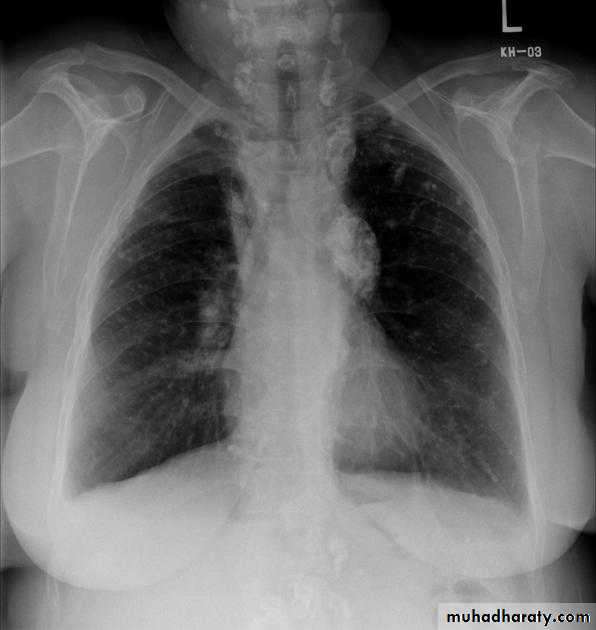

Hilar enlargement ( Bilateral )

1) Expiratory film2)LAP –hematological malignancy(leukemia, lymphoma ..)

-infections ( whooping cough or TB ?)

3) Vascular causes

Hilar enlargement ( unilateral )

1)Apparent –rotation-scoliosis

2) LAP